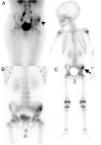

La gammagrafía (fig. 2) demostró la llegada simétrica del trazador a los miembros inferiores, con aumento de la vascularización e incremento patológico de la actividad osteoblástica en la pala ilíaca izquierda.

Gammagrafía ósea de pelvis y cuerpo completo en 3 fases. En la fase precoz, a los 5min de la inyección del radiotrazador, se visualiza un aumento de la vascularización en la hemipelvis izquierda (A, punta de flecha), que en la fase tardía, a las 3h postinyección, se correspondió con actividad osteoblástica en la pala ilíaca (B y C, flecha).